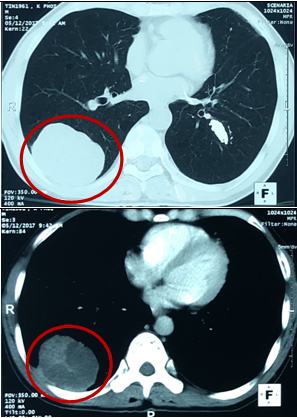

-   Cắt lớp vi tính lồng ngực: U thùy dưới phổi phải kích thước 56x81mm, ngấm thuốc sau tiêm. Khối mờ đỉnh phổi trái kích thước 28mm, nốt mờ nhỏ phân thùy lưỡi phổi trái.

Hình 1: Hình ảnh chụp cắt lớp vi tình lồng ngực

-   Chụp cắt lớp vi tính lồng ngực:

Trước điều trị: U phổi phải kích thước 56x81mm

Sau điều trị: U phổi phải kích thước 35x40mm

Trước điều trị: Khối mờ đỉnh phổi trái kích thước 28mm, nốt mờ thùy dưới phổi trái.

Sau điều trị: Khối mờ đỉnh phổi trái là dải xơ hóa, nốt mờ nhỏ thùy dưới phổi trái không còn.